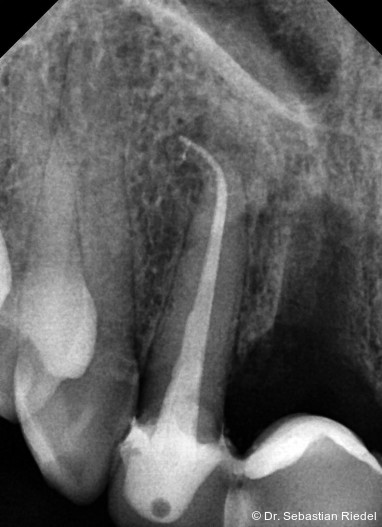

Foto: Dr. Sebastian Riedel

Im Rahmen der Diagnostik und unter Einbeziehung sinnvoller Technik muss eine Vorstellung davon entwickelt werden, WAS mechanisch bearbeitet werden soll. Daraus kann sich die Einsicht ergeben, WIE es bearbeitet werden kann. Zentrale Kriterien für die Auswahl der Wurzelkanalinstrumente sind die Effizienz und die Sicherheit eines Feilensystems unter den gegebenen Umständen. Daneben sind die Kosten, die Einflüsse auf die Zahnsubstanz und die Voraussetzungen für eine optimale Wurzelkanalfüllung Faktoren für die Beantwortung der Frage, ob ein System geeignet ist, eine zeitgemäße endodontische Behandlung zu ermög­lichen.

Eines sollte im Rahmen der Endodontie stets klar sein: Die mechanische Präparation des Wurzelkanalsystems dient nicht als Selbstzweck, sondern explizit der effizienten und effektiven Desinfektion durch geeignete Spüllösungen. Die Präparationsinstrumente – und nichts anderes sind die Wurzelkanalinstrumente – haben dabei die Aufgabe, die Wurzel­kanäle ohne maßgebliche anatomische Veränderungen so vorzubereiten, dass eine relevante Menge an Desinfektionsflüssigkeit alle Kanal­anteile bis zum Apex durchströmen kann.